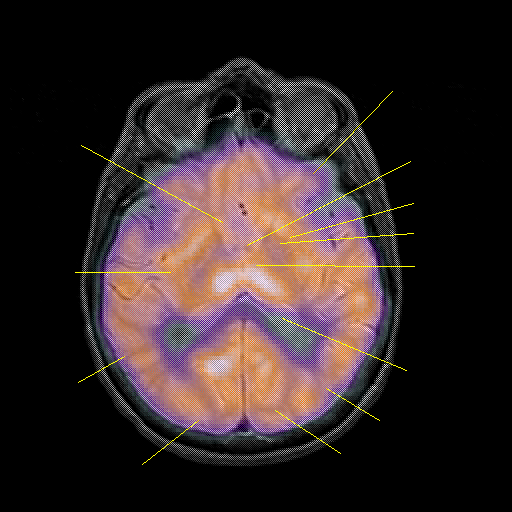

overlay : Slice 28

Slice 28

Pointers

Labeled